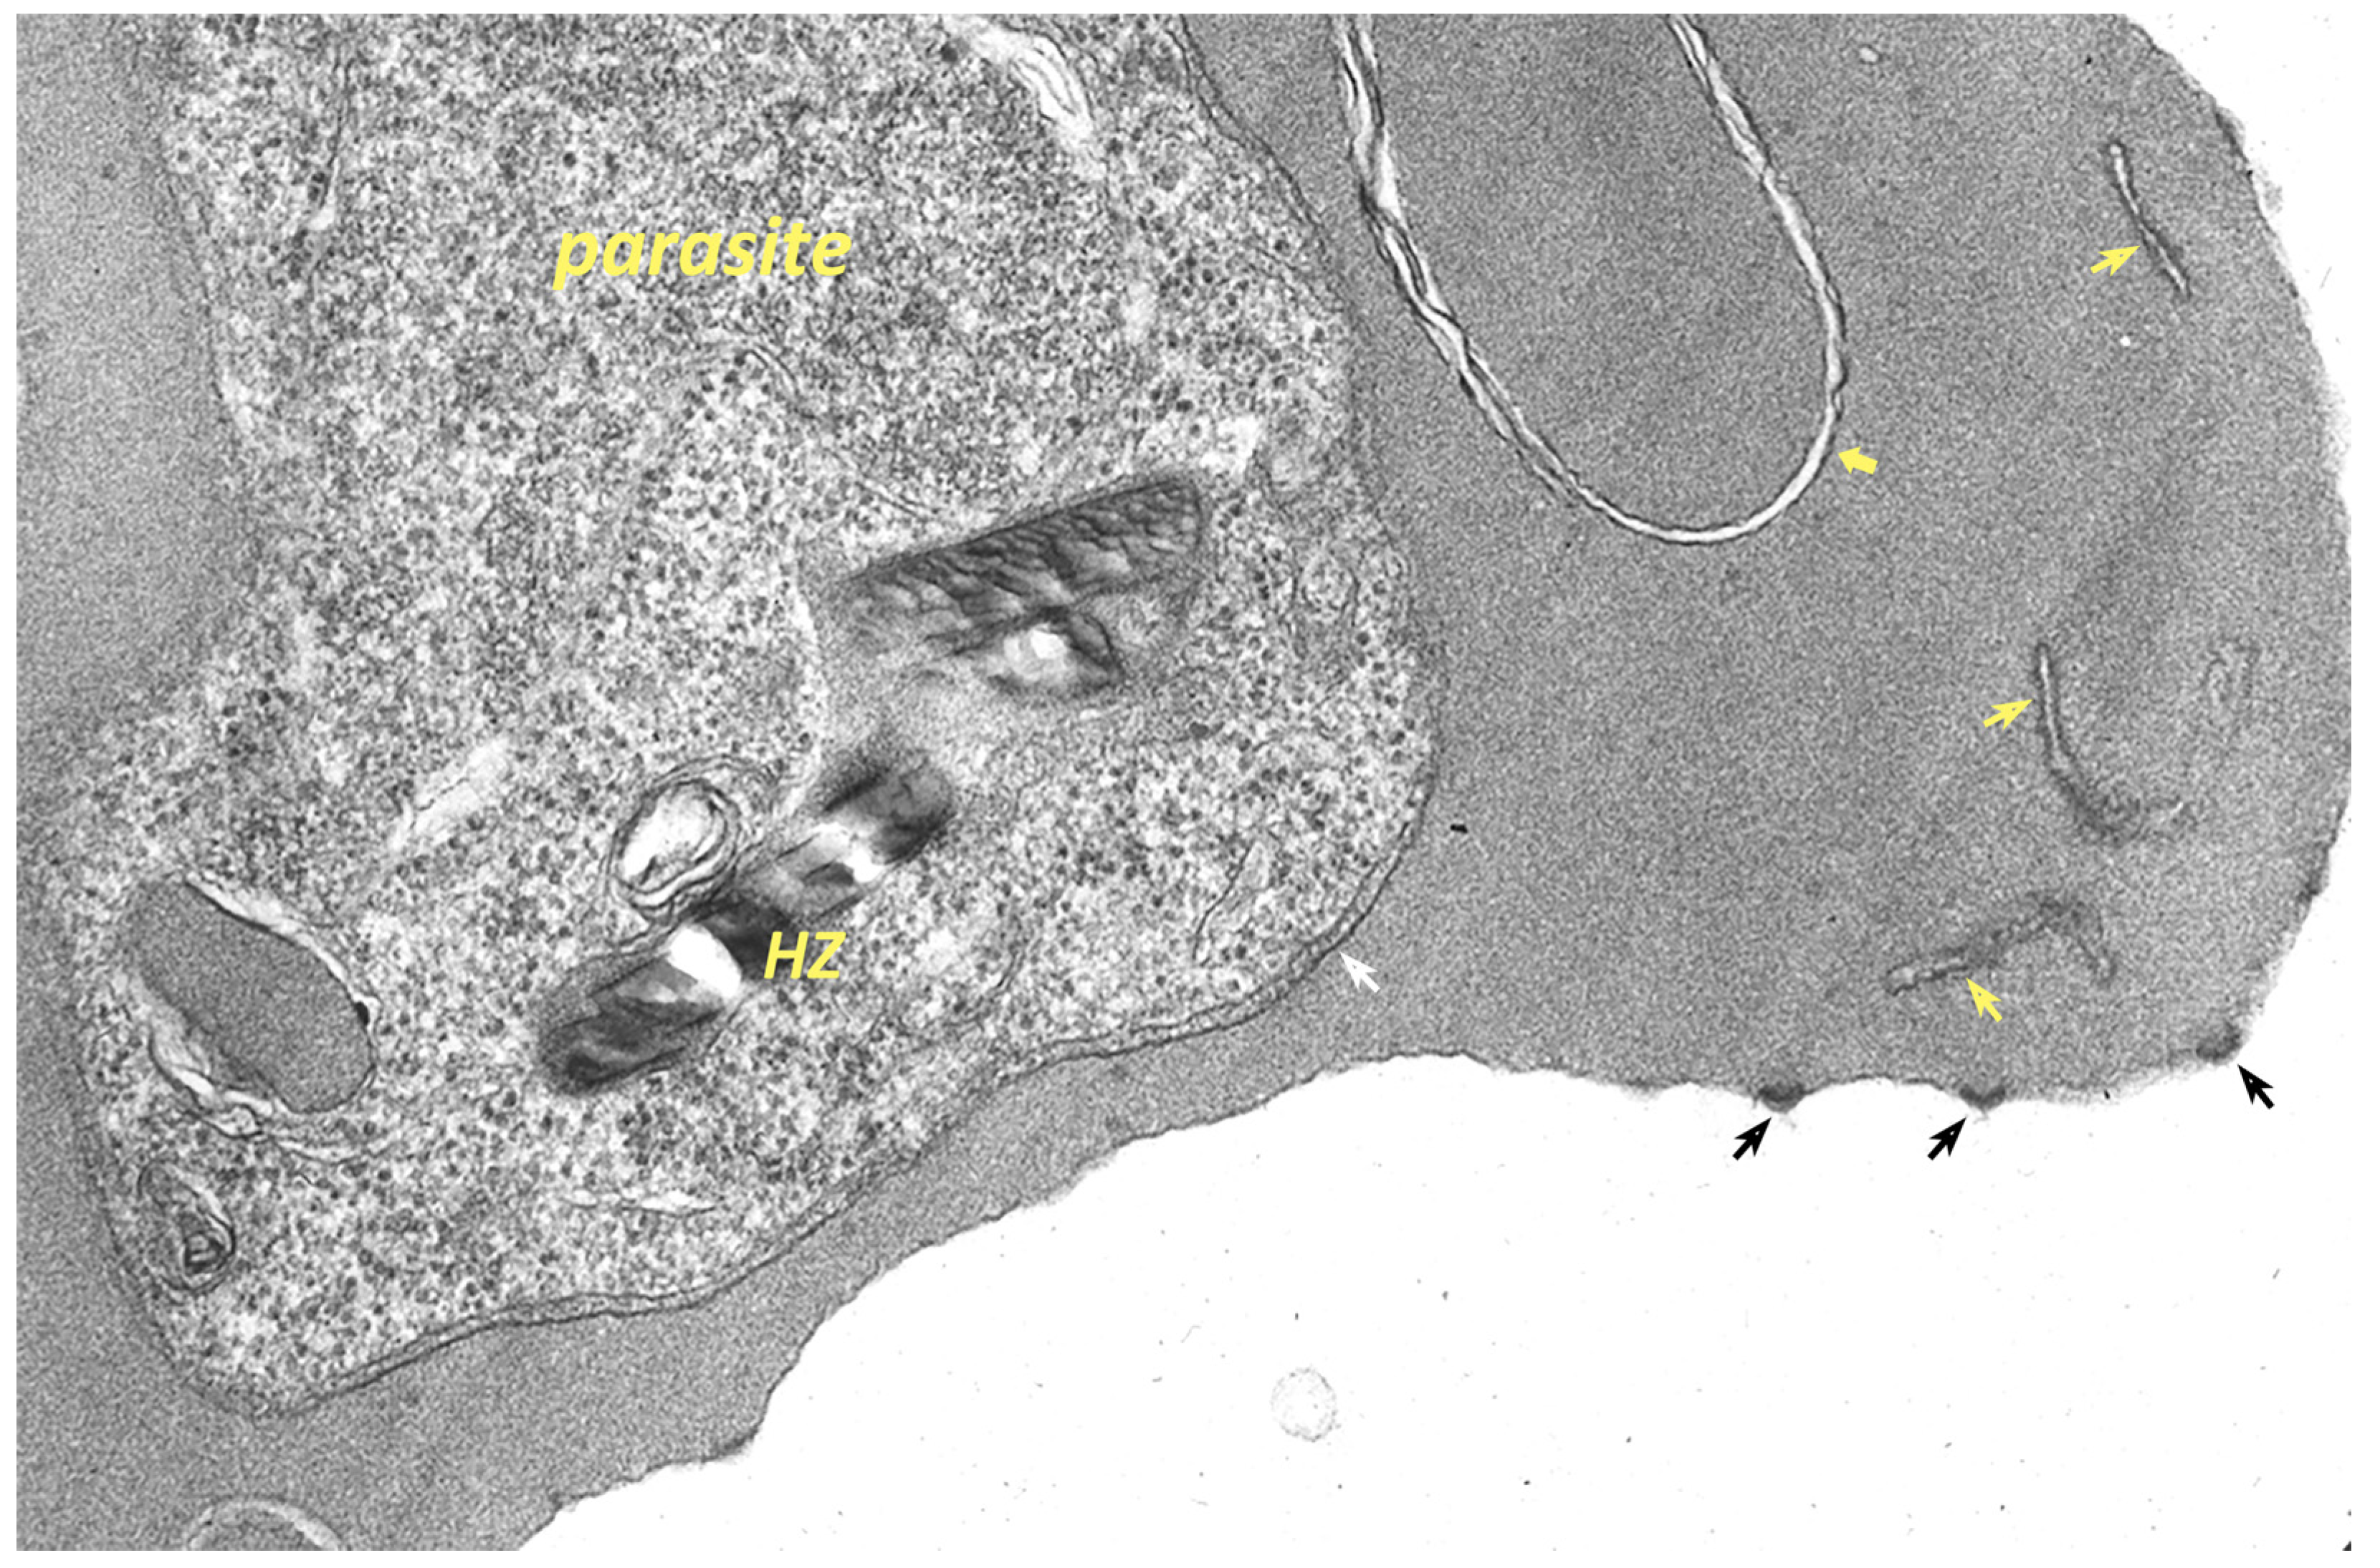

9. Remodeling the Host Erythrocyte by the Malaria Parasite

9.3. Extraparasite Trafficking within the Erythrocyte Cytoplasm